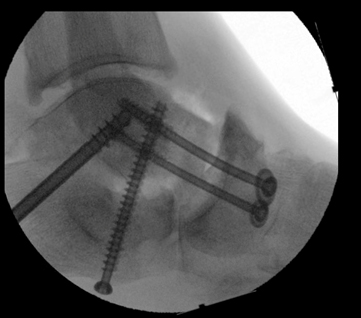

TOTAL ANKLE REPLACEMENT :: ORIF CALCANEUS :: ORIF ANKLE FRACTURE DISLOCATION :: COMPLEX BUNION AND LESSER TOE CORRECTION :: TALUS FRACTURE -1 :: TALUS FRACTURE -2 :: LISFRANC REPAIR :: COMPLEX TRIPLE ARTHRODESIS 1 :: COMPLEX TRIPLE ARTHRODESIS 2 :: MINIMALLY INVASIVE BUNION REPAIR 1 :: MINIMALLY INVASIVE BUNION REPAIR 2 :: ARTHROSCOPIC CARTILAGE REPAIR :: TENEX SPUR DEBRIDEMENT :: Haglunds Debridement and Achilles Repair